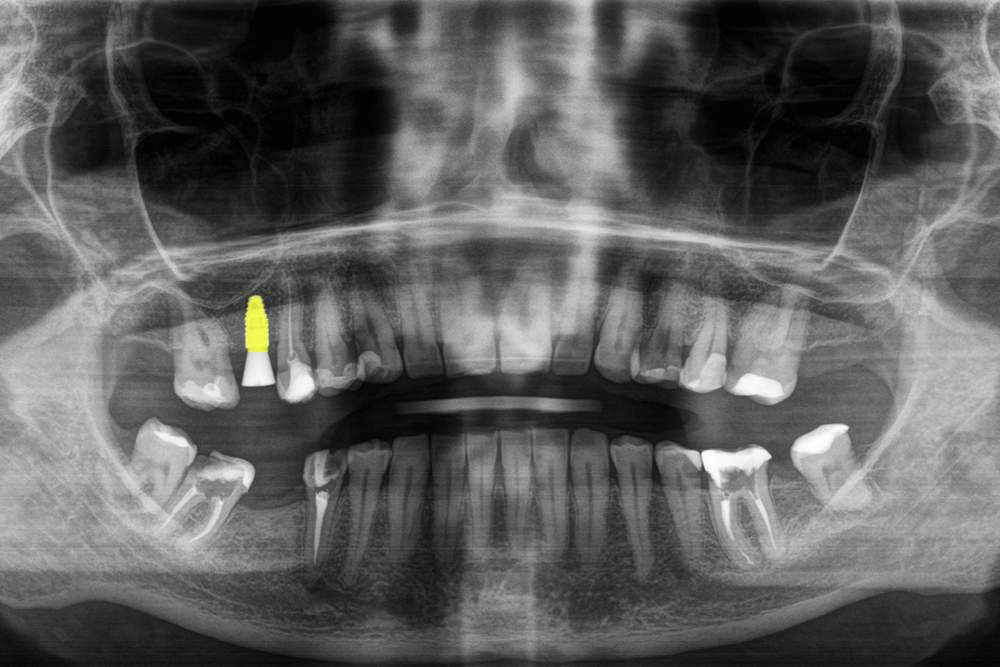

Во время консультации врач увидел на КТ-снимке отсутствие зуба 1.6 (на верхней челюсти справа), зуба 3.7 (на нижней челюсти слева), на место которого сместился зуб 3.8 (вот почему не стоит спешить удалять "восьмерки", если нет прямых показаний) и зуба 4.6 (на нижней челюсти справа), на место которого мигрировал зуб 4.7.

- установить только один имплант в области зуба 1.6 (на верхней челюсти справа)